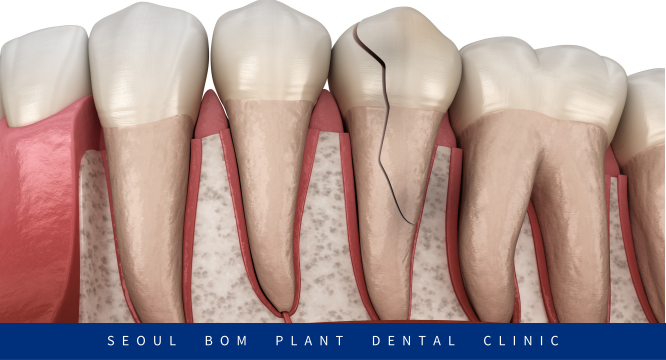

치관 / 치근 파절

치아 머리인 치관과

뿌리인 치근이 동시에 파절된 경우로

보통은 수평보다는

수직으로 파절이 많이 발생하는데요.

이 경우에는 안타깝게도

치아를 살리기 쉽지 않기 때문에

발치 후 보철치료나 임플란트로

수복을 진행해 주어야 합니다.

치근 파절

보이지 않는 곳에서 균열이 시작되므로

발견이 쉽지 않고 치아가 흔들리거나

염증이 생길 수 있는데요.

치관 치근 파절과 마찬가지로

발치를 진행할 수밖에 없습니다.

위 사례의 환자분과 같이

치아 치근부터 세로로 금이 가는

수직 치근 파절이 발생하면 벌어진 부위로

치수 괴사가 일어나게 됩니다.

결국 염증이 생겨 주변 뼈가 녹았고

발치가 불가피한 상황이

올 수밖에 없습니다.